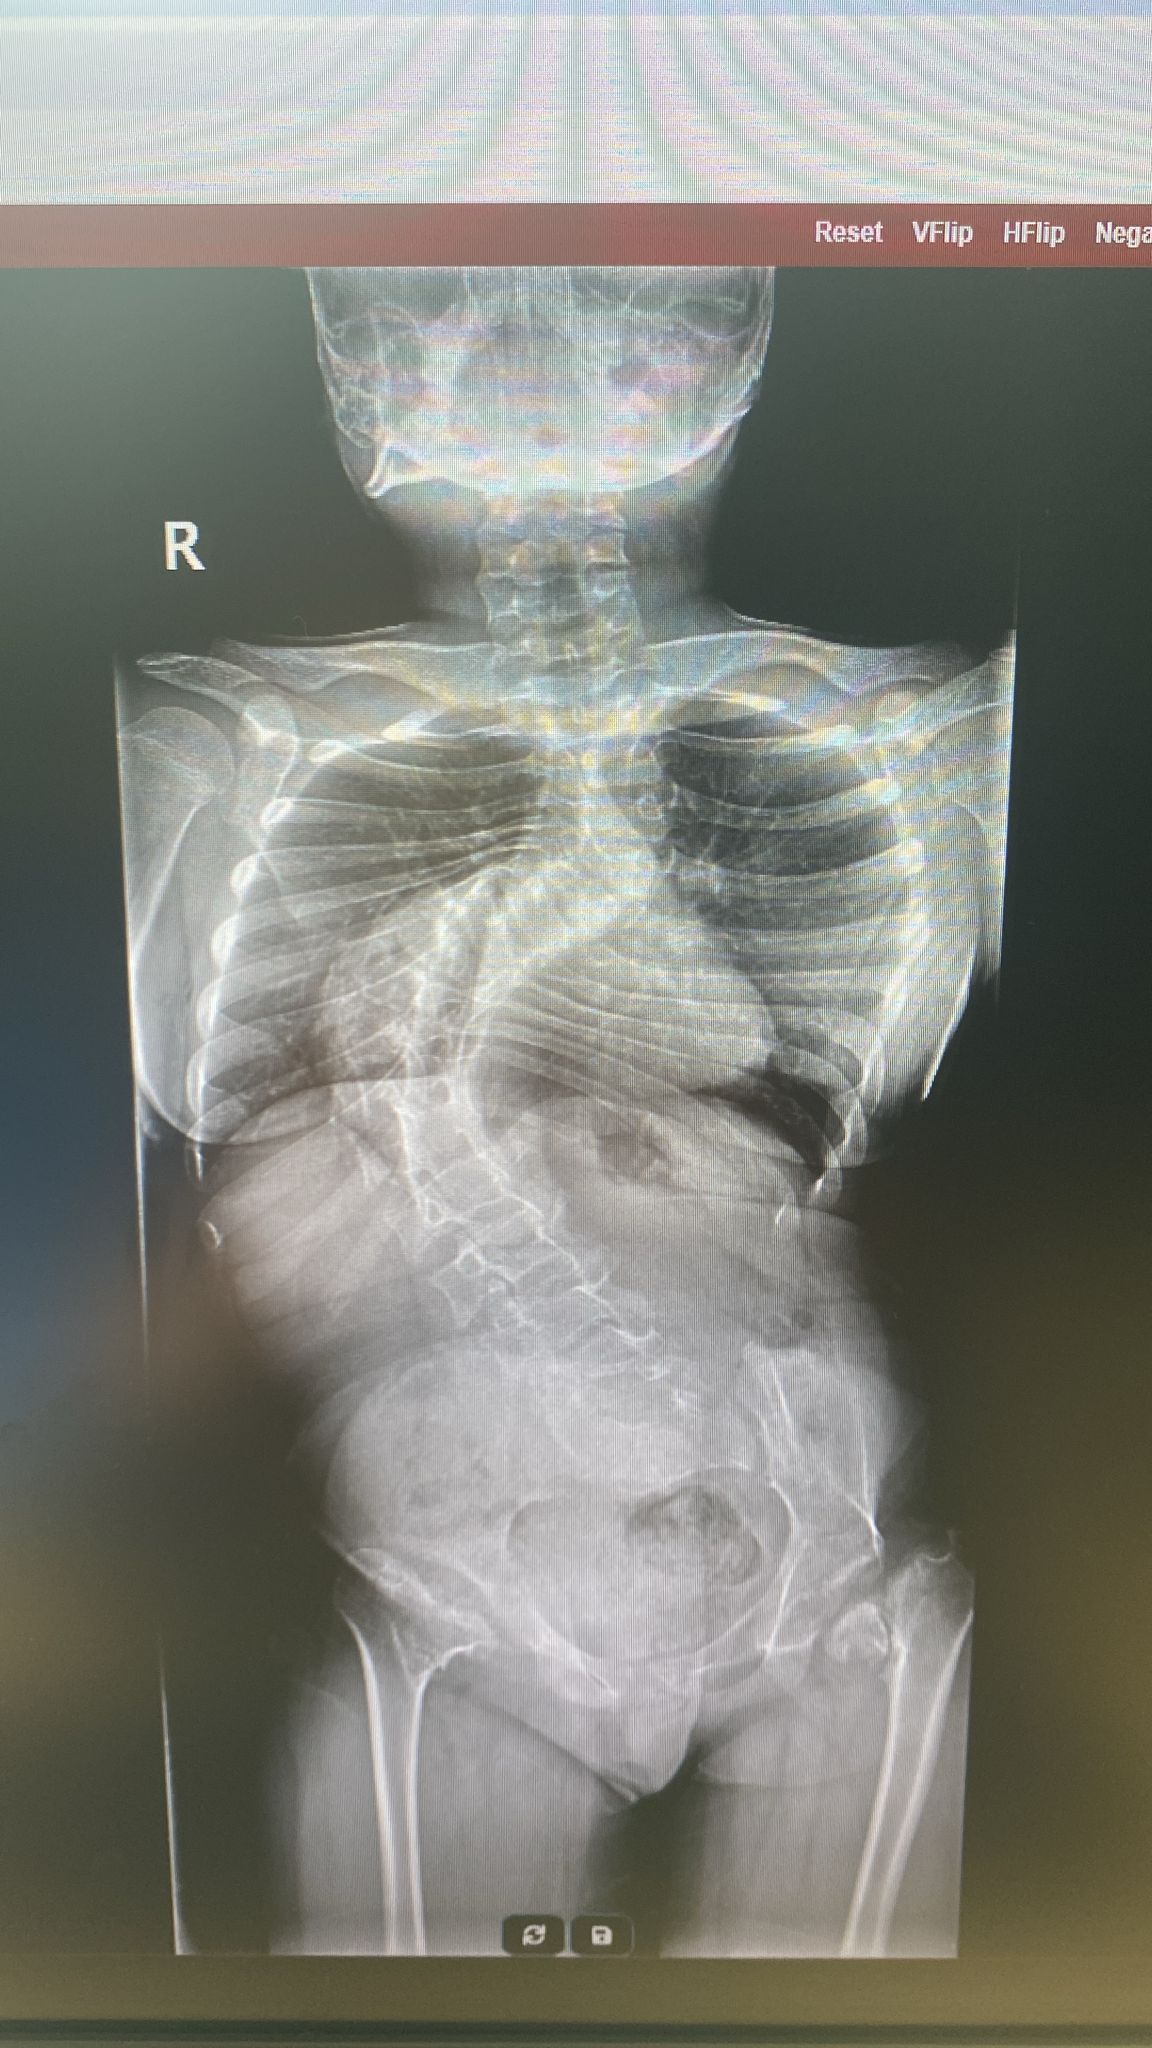

Pandemi döneminde kontrol sürecine 1 yıl ara verildi. Daha sonra kontrole götürülen Akbay'ın skolyoz eğrilik derecesinin yüzde 85'e kadar çıktığı belirtildi.

1,5 yıl boyunca doktor aradıklarını ancak riskli olduğu gerekçesiyle kızını ameliyat edecek bir doktor bulamadıklarını söyleyen baba Abdullah Akbay, bu süreçte Kardelen'in skolyoz eğrilik derecesinin 96'ya ulaştığını belirtti.

Ama Halil Hoca, 'Sen varsan, ben de elimi taşın altına koyacağım' dedi. Şu an eğrilik derecem 96 ve omuriliğim akciğerimi içine girmeye başlamış. Derecem biraz daha yükselirse, ameliyat şansım da kalmayacak ve hayati riskim artacak. Ameliyatın maliyeti 4 milyon TL ve bir an önce bu parayı toplamamız gerekiyor. Çünkü en kısa sürede ameliyat girmem gerekiyor. Çok küçük yaştan beri bu rahatsızlığı çektiğim için geri kalan hayatımda sağlıma kavuşmak istiyorum. Ameliyatla kurtulma şansım var; bu ihtimali değerlendirmek istiyorum" dedi